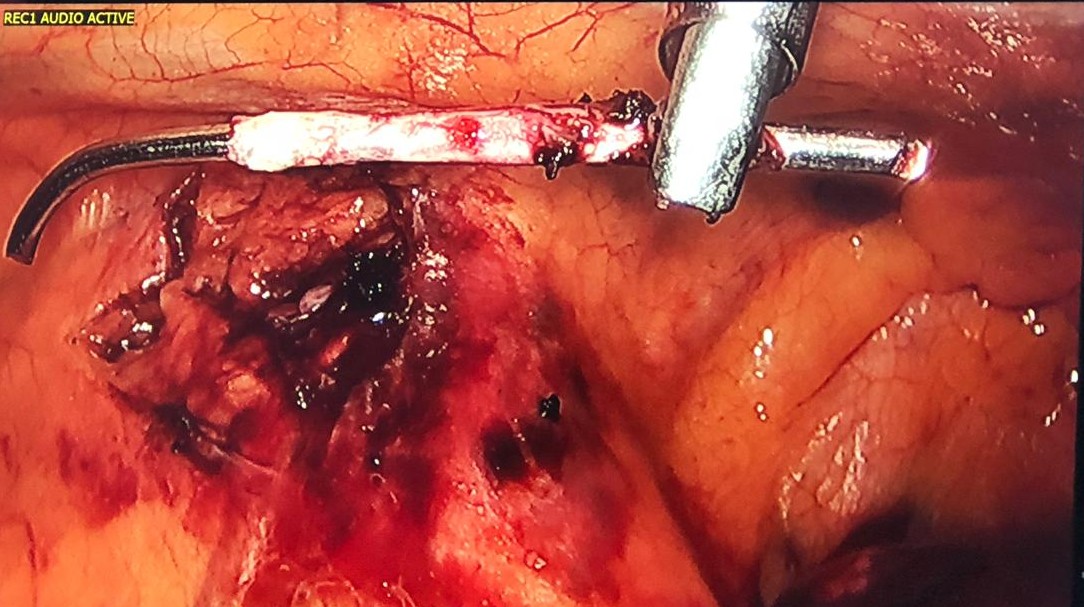

Figure 6. K-wire completely dissected from the lung. One can observe the phrenic nerve very close to the K-wire.

Figure 7. With the aid of an energy device, the authors dissected the tissues around the foreign body, in front of the phrenic nerve like in a thymectomy, and the K-wire was easily removed. It was not hooked to the left brachiocephalic vein.